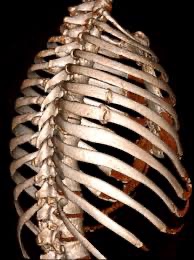

Contributors: Travis Barlock MD, Jeffrey Olson MS4 Feel free to use the cases below for your own practice. All of the scenarios are completely made up and designed to hit several teaching points. Case 1 25 M, presents to the ED with chest pain. Stabbing, started a few hours ago, substernal. Thinks it is GERD. After 2-3 minutes, pain worsens and radiates to the back. VS: BP 125/50 (Right arm 190/110). HR 120. RR of 18. Sat 98% on RA. Additional VS: Temp of 37.2, height of 6'5", BMI of 18. PMH: None, doesn't see a doctor. Meds: None FH: Weird heart thing (Mitral Valve Prolapse), weird lung thing (spontaneous pneumothorax), tall family members with long fingers and toes Physical Exam: Cards: Diastolic decrescendo at the RUSB, diminished S2. UE pulses are asymmetric, LE pulses are asymmetric, carotid pulses are asymmetric, BP is asymmetric MSK: Knees, elbows, and wrists are hypermobile. Imaging: CXR #1 normal, #2 widened mediastinum (no read yet but shows widened mediastinum), POCUS shows small effusion CTA/MRA doesn't come back until after the case. ECG: Sinus Tach Labs: NT-proBNP 500 pg/mL D-Dimer: 7000 ng/L CBC: Hemoglobin: 13.5 g/dL, WBC: 20,000/µL, Platelets: 250,000/µL Chem 7: Na 138, K, 5.7, Cl 102, Bicarb 17, BUN 45, Creatinine: 3.5 mg/dL, Glucose: 180 LFTs: Albumin 2.4, Total protein 5.5, ALP: 140, AST: 3500, ALT: 2800, TBili: 3.2, DirectBili: 2.4, Ca: 7.8 LDH: 2200 PT: 20.5, INR: 2.2, Fibrinogen: 170 5th gen High-Sensitivity Troponin: <3 Lactate: 7 mmol/L VBG: pH 7.22, paCO2 28, bicarb 15 Notes: Can have patient crash somewhere in middle and show 2nd xray Case 2: A 67-year-old female is brought to the ED by her daughter due to progressive weakness, confusion, and fatigue that have worsened over the past week. Unable to get out of bed and has become increasingly lethargic. Also having some nausea, constipation. The daughter denies any preceding illness, recent trauma, or travel. Does not know her meds but will head home to get them after talking with you. VS: BP 88/55 mmHg, HR 110, RR 20, O2 Sat 98% on room air. Additional VS: Temp 36.8°C. PMH: Hypertension, osteoarthritis, and depression. Physical exam: General: Thin, somnolent but arousable. HENT: Dry mucous membranes Neuro: Confused, A&Ox1 (self), hyporeflexia Labs (Includes many that would not return in the ED in case you want to take this case forward to the floor) CBC: WBC 9,500, Hb 16.5, Hct: 50%, Platelets 220,000 Chem7: Na 129, K 2.1, Cl 95, HCO3 34, Creatinine 1.6, BUN 40, Glucose 115 LFTs: normal Magnesium: 1.1 Calcium: 10.8 mg/dL (corrects to 12.8) iCal: 3.2 Phosphate: 2.3 mg/dL Albumin: 2 BUN:Cr ratio: 25 VBG: pH: 7.49, PaCO2 45, HCO3: 34 Lactate: 2.8 Serum Osmolality: 276 mOsm/kg (Osmolal gap of 2) Urine Osmolality: 550 mOsm/kg Urine Sodium (UNa): 10 mEq/L (low). Urine Potassium (UK): 25 mEq/L (elevated). Urine Chloride (UCl): 12 mEq/L (low). Urine Magnesium (UMg): 20 (Elevated). Urine Calcium (UCa): 50 in 24 hrs (Low) 100 cc of urine with foley FeNa Plasma renin activity: 15 mg/mL/hr (elevated), Aldosterone: 25 ng/dL (Elevated), ADH: Elevated, Diuretic screen: Positive for thiazides PTH: 8 (low), HsTrop: 32, Cortisol and ACTH: Normal. EKG: Hypokalemia features CXR: Normal Renal US: shows stones Improves with fluids Note: Can have daughter return with med list at some point including HCTZ, ibuprofen, and sertraline Case 3: Patient Presentation EMS Report: A 27-year-old male involved in a high-speed motorcycle collision is brought to the emergency department by EMS. The patient was found unconscious at the scene with evidence of severe thoracic and extremity trauma. He was intubated en route for airway protection due to altered mental status (GCS 7). VS: HR 130, BP 90/60, RR: bagging at 12 bpm, satting 88% on 100% FiO2 Primary Survey Airway: Endotracheal tube in place. Breathing: Decreased breath sounds on the left side with visible chest asymmetry and paradoxical chest wall movement. Circulation: Mottled extremities noted, with significant deformity of the right thigh. Pulses are diminished in the right leg Disability: GCS remains 7 (E1 V2 M4). Pupils equal and reactive. Exposure: Full-body examination reveals an open fracture of the right femur, multiple abrasions, and bruising over the chest wall. Vent alarms Peak Inspiratory Pressure (PIP) 40 cm H₂O (elevated) Plateau Pressure (Pplat) 35 cm H₂O (elevated) EtCO₂ (End-Tidal CO₂) 55 mmHg High-Pressure Alarm Triggering frequently Glucose 120 CBC: Hgb 8.9, Hct 27, WBC 14.2, platelets 220,000 VBG: pH 7.28, pCO2 33, bicarb 18, lactate 4.5 CXR with tension pneumothorax Patient improves after chest tube, pigtail catheter, or needle decompression. Ready to be transferred upstairs and O2 starts tanking again Vent alarms- second episode Peak Inspiratory Pressure (PIP) 35 cm H₂O (elevated) Plateau Pressure (Pplat) 30 cm H₂O (elevated) EtCO₂ (End-Tidal CO₂) 20 mmHg HR: 140, satting 84%, temp 38.5, ABG: pH 7.32, pCO₂ 30 mmHg, pO₂ 60 mmHg on 100% FiO₂, HCO₃⁻ 18 mmol/L (hypoxemia and metabolic acidosis). D-dimer: Elevated Thrombocytopenia: Platelets 90,000/µL. US shows blown right ventricle ECG shows new RBBB CT PE: Ground glass opacities, consolidation, centrilobular nodules, septal thickening, and fat-attenuating lesions. Note: Management is largely supportive care so once the diagnosis is made, end the case. References Carroll MF, Schade DS. A practical approach to hypercalcemia. Am Fam Physician. 2003 May 1;67(9):1959-66. PMID: 12751658. Coelho SG, Almeida AG. Marfan syndrome revisited: From genetics to the clinic. Rev Port Cardiol (Engl Ed). 2020 Apr;39(4):215-226. English, Portuguese. doi: 10.1016/j.repc.2019.09.008. Epub 2020 May 18. PMID: 32439107. Palmer BF. Metabolic complications associated with use of diuretics. Semin Nephrol. 2011 Nov;31(6):542-52. doi: 10.1016/j.semnephrol.2011.09.009. PMID: 22099511. Reed MJ. Diagnosis and management of acute aortic dissection in the emergency department. Br J Hosp Med (Lond). 2024 Apr 30;85(4):1-9. doi: 10.12968/hmed.2023.0366. PMID: 38708978. Roberts DJ, Leigh-Smith S, Faris PD, Blackmore C, Ball CG, Robertson HL, Dixon E, James MT, Kirkpatrick AW, Kortbeek JB, Stelfox HT. Clinical Presentation of Patients With Tension Pneumothorax: A Systematic Review. Ann Surg. 2015 Jun;261(6):1068-78. doi: 10.1097/SLA.0000000000001073. PMID: 25563887. Rothberg DL, Makarewich CA. Fat Embolism and Fat Embolism Syndrome. J Am Acad Orthop Surg. 2019 Apr 15;27(8):e346-e355. doi: 10.5435/JAAOS-D-17-00571. PMID: 30958807. Produced by Jeffrey Olson, MS4 Special thanks to Evan Fisch MD Get your tickets to Tox Talks Event, Sept 11, 2025: https://emergencymedicalminute.org/events-2/ Donate: https://emergencymedicalminute.org/donate/